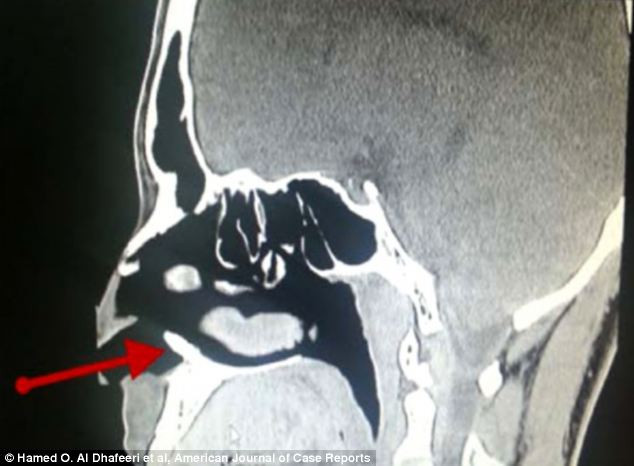

A mers la spital din cauza unor probleme nazale. Descoperirea facuta la radiografie i-a surprins si pe medici. FOTO

Un barbat de 22 de ani, din Arabia Saudita, a mers la medic din cauza unor probleme la nas. La radiografie doctorii au ...